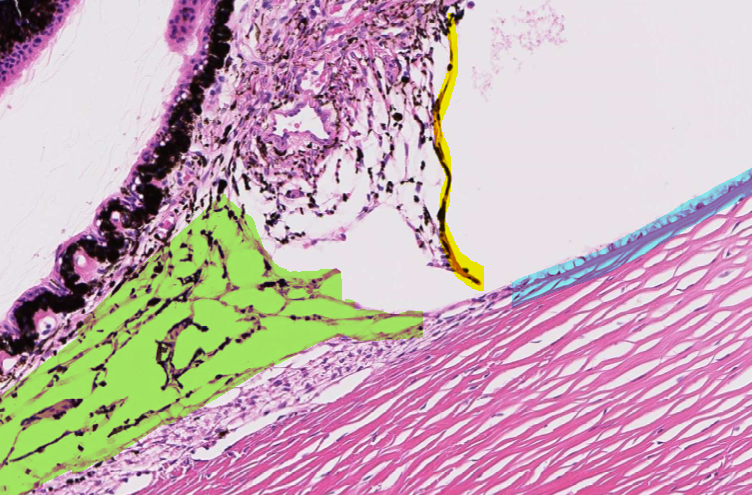

4

Q

This is normal, healthy tissue of the eye.

What are the highlighted structures?

Green = ____

Yellow = ____

Blue = ____

A

Green = trabecular meshwork

Yellow = pectinate ligament

Blue = descemet’s membrane

How well did you know this?